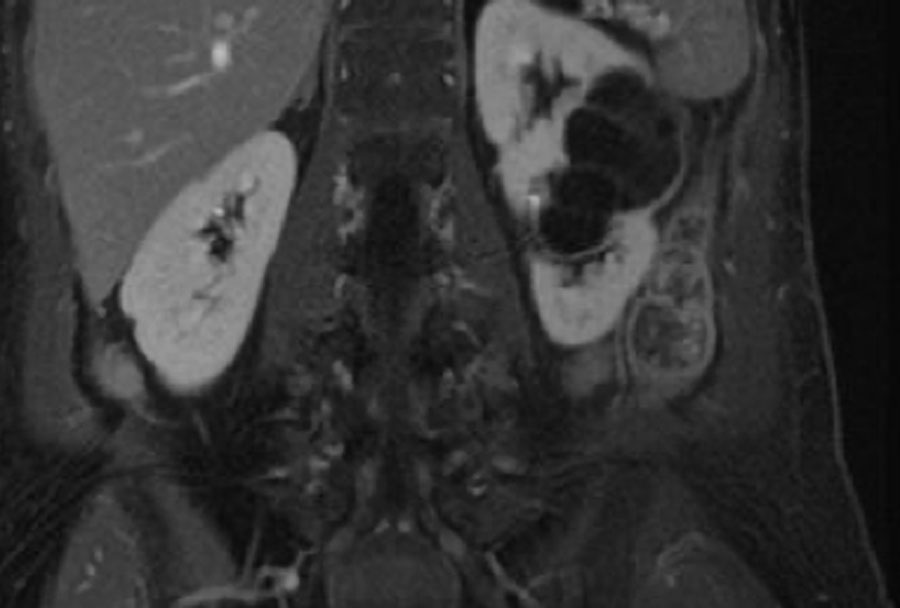

Có một khối dạng nang ở thận phải với nhiều (> 4) vách ngăn mỏng, nhẵn, có ngấm thuốc.

Tổn thương được phân loại là Bosniak IIF.